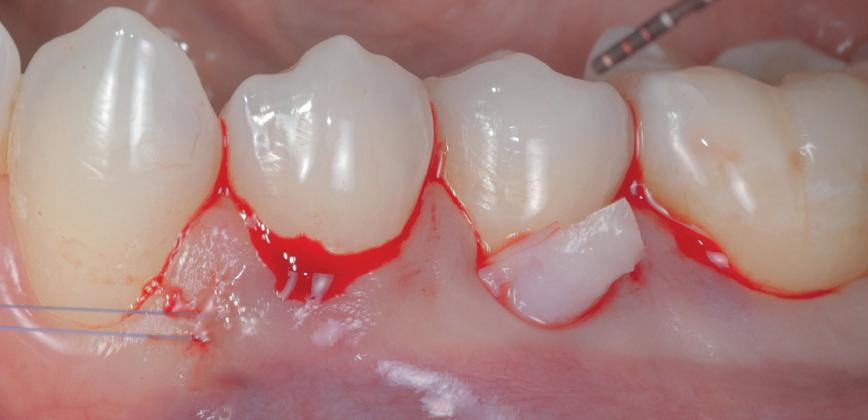

Gingivectomia

Se practică îndepărtarea excizională a țesutului gingival. Vârful caninului trebuie să fie la nivelul sau sub joncțiunea mucogingivală (mucogingival junction, MGJ). Această

procedură este indicată dacă există o zonă largă de țesut gingival keratinizat și se efectuează fie cu un instrument Kirkland, fie cu o lamă 15 cu bizou extern. Dacă vârful caninului este situat coronar față de joncțiunea smalț-cement (cementoenamel junction, CEJ) a incisivului lateral, atunci se poate efectua gingivectomia. La finalizarea procedurii, cel puțin 3 mm din țesutul gingival keratinizat ar trebui să fie poziționat apical de CEJ. Cel puțin două treimi din coroana clinică ar trebui să fie expuse pentru a permite amplasarea bracketului. Un dezavantaj al acestei tehnici constă în necesitatea repetării procedurii dacă țesutul gingival se reface.